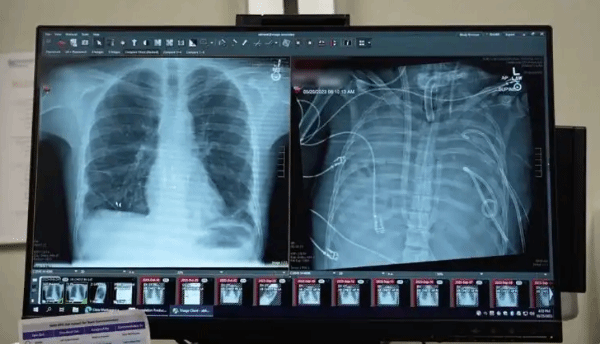

最近,美国西北大学的科学家分享了一个案例,一名患者在肺部切除和肺移植时间间隔期间,靠外部含氧血液存活了48小时。

该系统由美国西北大学范伯格医学院团队开发。研究团队指出,此前虽有患者在肺切除后依靠外部设备维持氧合,但那些设备无法维持心脏的正常血流和功能。因此,本次案例是全球首个真正意义上实现“无肺生存”的医疗突破。

33岁的重症患者因流感引发急性呼吸窘迫综合征,后又感染耐药菌,导致肺部严重化脓,并出现感染性休克及多器官衰竭。医疗团队为清除感染源,决定切除其双肺。在连接人工肺系统后,患者状况迅速好转,并于48小时后成功接受双肺移植。手术至今近三年,患者恢复良好,未出现排斥反应或肺功能受损。